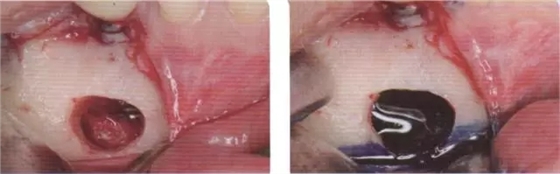

圖1 圖2

圖1 患者46牙根管再治療失敗,出現(xiàn)根尖炎癥,準(zhǔn)備拔除做即刻種植

圖2 小視野CBCT圖像顯示種植修復(fù)一年后的骨容解情況